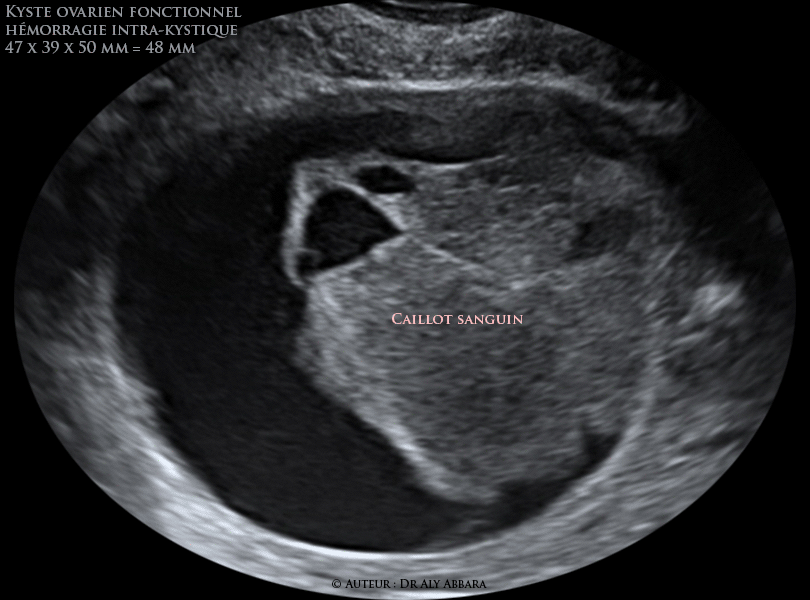

Kyste Ovarien Fonctionnel Hemorragie Intrakystique Prenant L Aspect Echographique D Une Fausse Cloison

Kystes Ovariens Fonctionnels Les Differents Aspects Echographiques De L Hemorragie Intra Kystiques